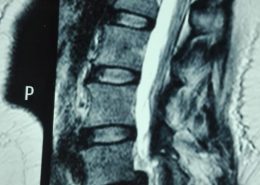

Latest Spine Fixation Technique